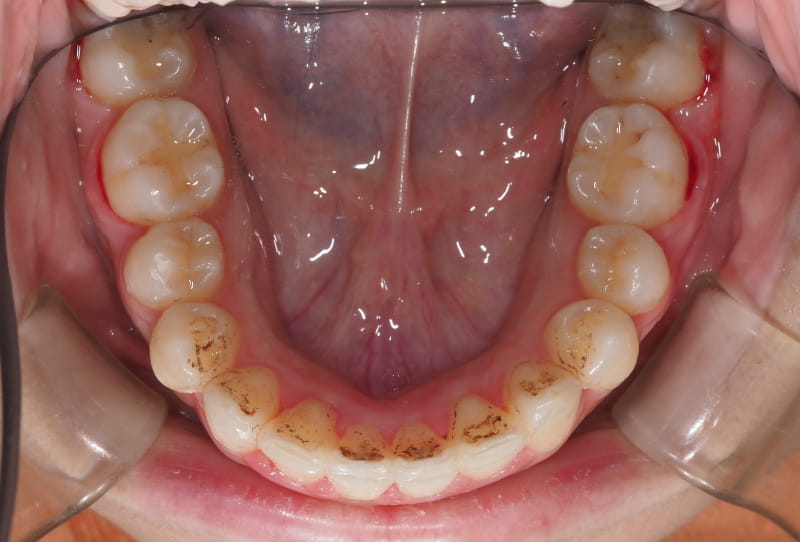

二、如果第一步判斷需要正畸治療,那麼就要檢查牙齒的情況,進行臨床資料的採集,隱形正畸需要的資料包括但不限於口掃、拍攝口腔全景的X光片、面像照以及口內照等視覺數字化檢查項目。

牙齒矯正案例 – 1

牙齒矯正案例 – 2

牙齒矯正案例 – 3

牙齒矯正案例 – 4

牙齒矯正案例 – 5

牙齒矯正案例 – 6

牙齒矯正案例 – 7

牙齒矯正案例 – 8